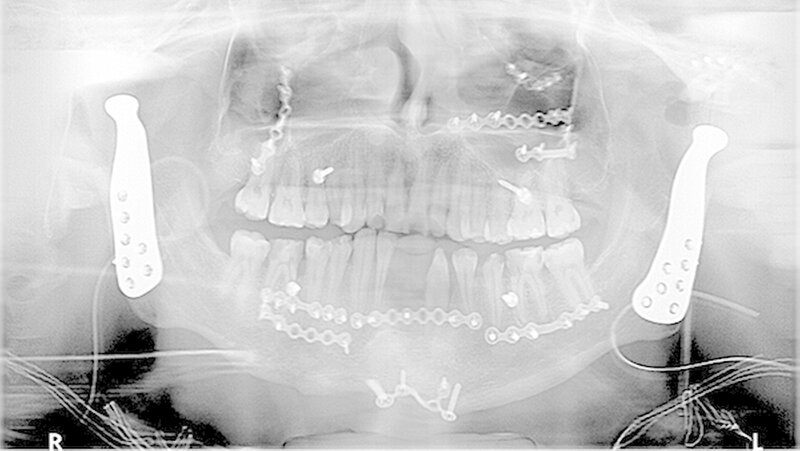

Dem Patienten wurde der totale Gelenkersatz beidseits mit auf der Basis der gewonnenen CT-Daten individuell erstellten Fossa-Komponenten aus einem speziellen Kunststoff (Ultra High Molecular Weight Polyethylene) und individuellen Gelenkkopfprothesen aus einer titanbeschichteten Chrom-Kobalt-Legierung vorgeschlagen (Biomet Microfixation Inc., Vertrieb Zimmer Biomet Deutschland GmbH). Der Patient und seine Angehörigen wurden in intensiven Gesprächen über die Vorteile und Risiken des Eingriffs aufgeklärt.

Nach Akzeptanz des Behandlungsplans wurden beidseits die TEPs (Totalendoprothesen) über jeweils einen präaurikulären und einen retromandibulären Zugang implantiert. Diese Prothesen wurden mit Schrauben mit exakt am CT-Datensatz definierten Schraubenlängen fixiert. Bei der Planung der Schraubenpositionierung wurde auch der Verlauf N. alveolaris inferior berücksichtigt und der Nerv geschont.

Vor der definitiven Fixierung der Prothesen wurden Dummys als Test eingesetzt, um eine optimale Positionierung der passgenauen finalen Prothesen zu erreichen (Abbildung 2 bis 9). Abbildung 10 a und 10b zeigen die postoperative Röntgenkontrolle.